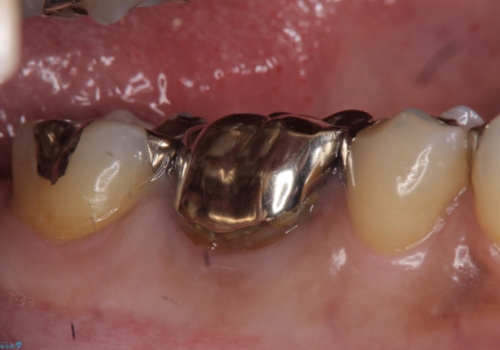

- 他院にて根尖病変があるため根管治療を勧められ当院にいらっしゃった方の症例です。

再根管治療を行い病変の縮小傾向を確認後、オールセラミッククラウンによる補綴を行いました。